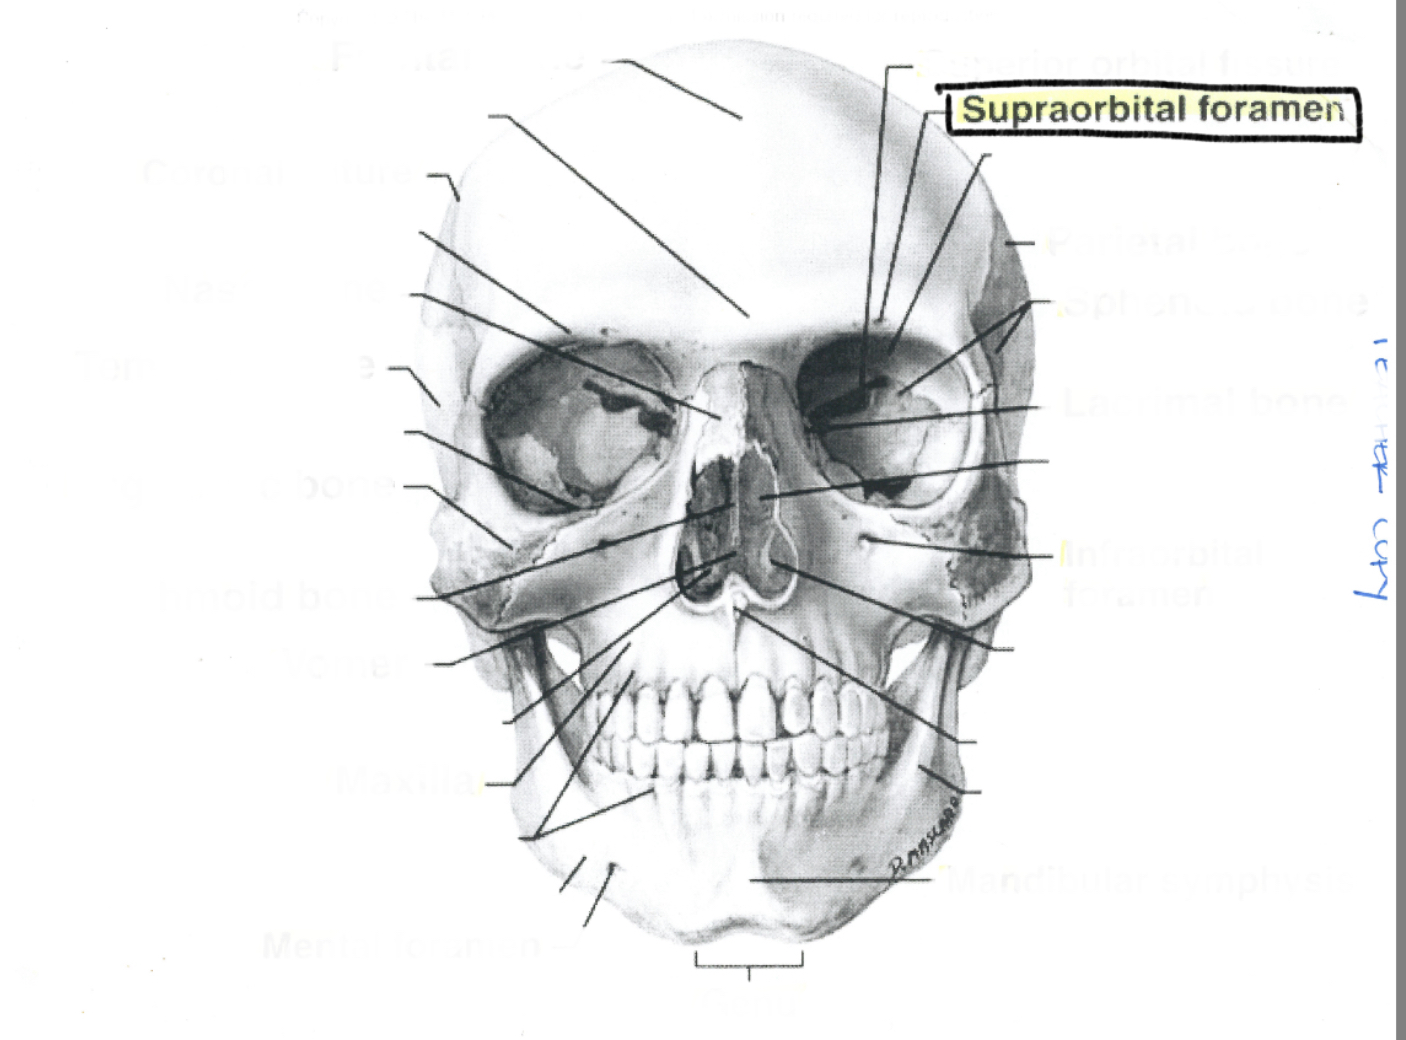

Supraorbital foramen

Supraorbital foramen